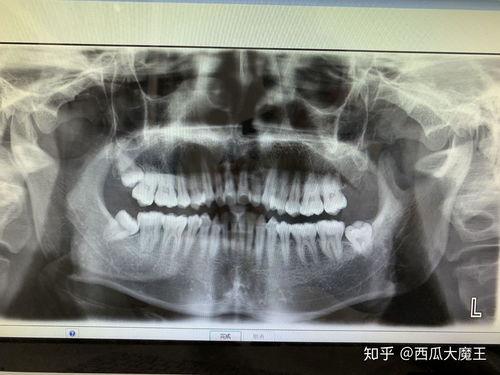

在拔牙前,医生会先给你进行口腔检查,确认智齿的位置和生长情况。医生会给你进行局部麻醉,让你在拔牙过程中不会感到疼痛。